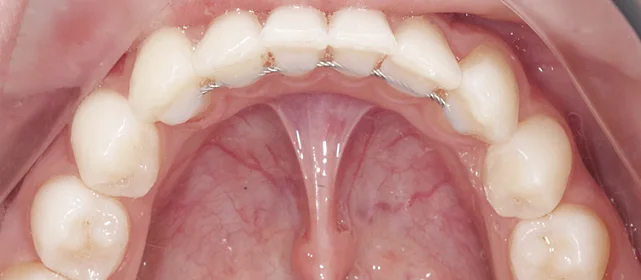

Зубы выровнены, смыкание нормализовано. Установлены несъёмные ретейнеры на обе челюсти, сняты сканы для ретенционных кап.

Решение: Поставили прозрачные элайнеры Click — начали с компактного набора из 20 кап. Основной комплект сделал основной объем работы, но для финальной доводки понадобился дополнительный набор из 10 кап. Итого 30 кап за 23 месяца. Результат — зубы на месте, смыкание в норме. Зафиксировали ретейнеры на обе челюсти, сняли сканы для ретенционных кап.

Небольшой по объёму случай — 20 кап в основном наборе. Этого хватило для основного выравнивания, но финальная коррекция смыкания потребовала ещё 10 кап. Предпочитаю доработать, чем оставить компромиссный результат. 30 кап за 23 месяца — спокойный темп, без спешки.